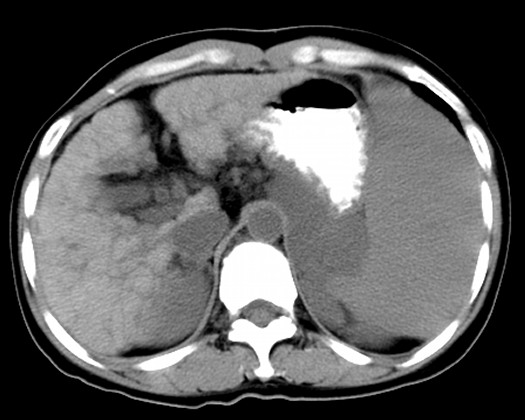

图 4 灰阶超声示脾脏增大,脾梗死( s 脾脏)图 3 灰阶超声示肝硬化

图 3 灰阶超声示肝硬化,腹腔积液( l 肝脏 f 腹腔积液)图 2 彩色